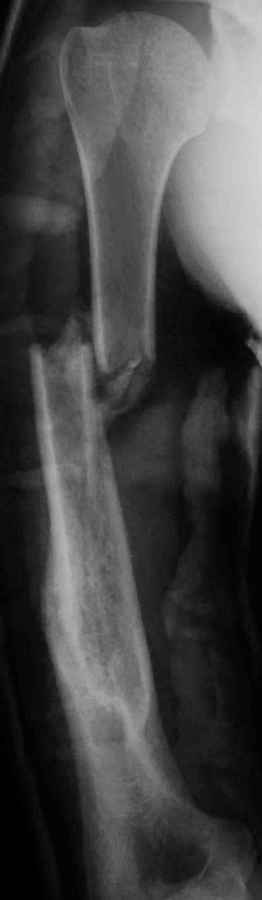

[Ortho] Результат консервативного лечения короткого косого перелома диафиза плеча врачами общей практики в условиях развивающейся страны у больного low social class

Последний перелом плеча – ДТП 2 мес назад. В связи с дефицитом как специалистов – ортопедов, так и операционного времени в принципе больной был осмотрен в приемном покое врачом общей практики, наложена U-образная гипсовая повязка и отправлен домой. Я впервые увидел больного через 6 нед после травмы, сделал снимки и снял повязку. Фотографии больного  - 2 мес после травмы. снимки - при травме и через 6 недель

Вывод: Если плечо не трогать, оно нормально срастается.

Тот же самый вывод наукообразно: данное клиническое наблюдение свидетельствует, что консервативное лечение переломов диафиза плеча является патофизиологически оптимальным, приводит к удовлетворительному функциональному результату и явлеяется наиболее экономически щадащим как для больного, так и для системы государственного здравоохранения в целом.